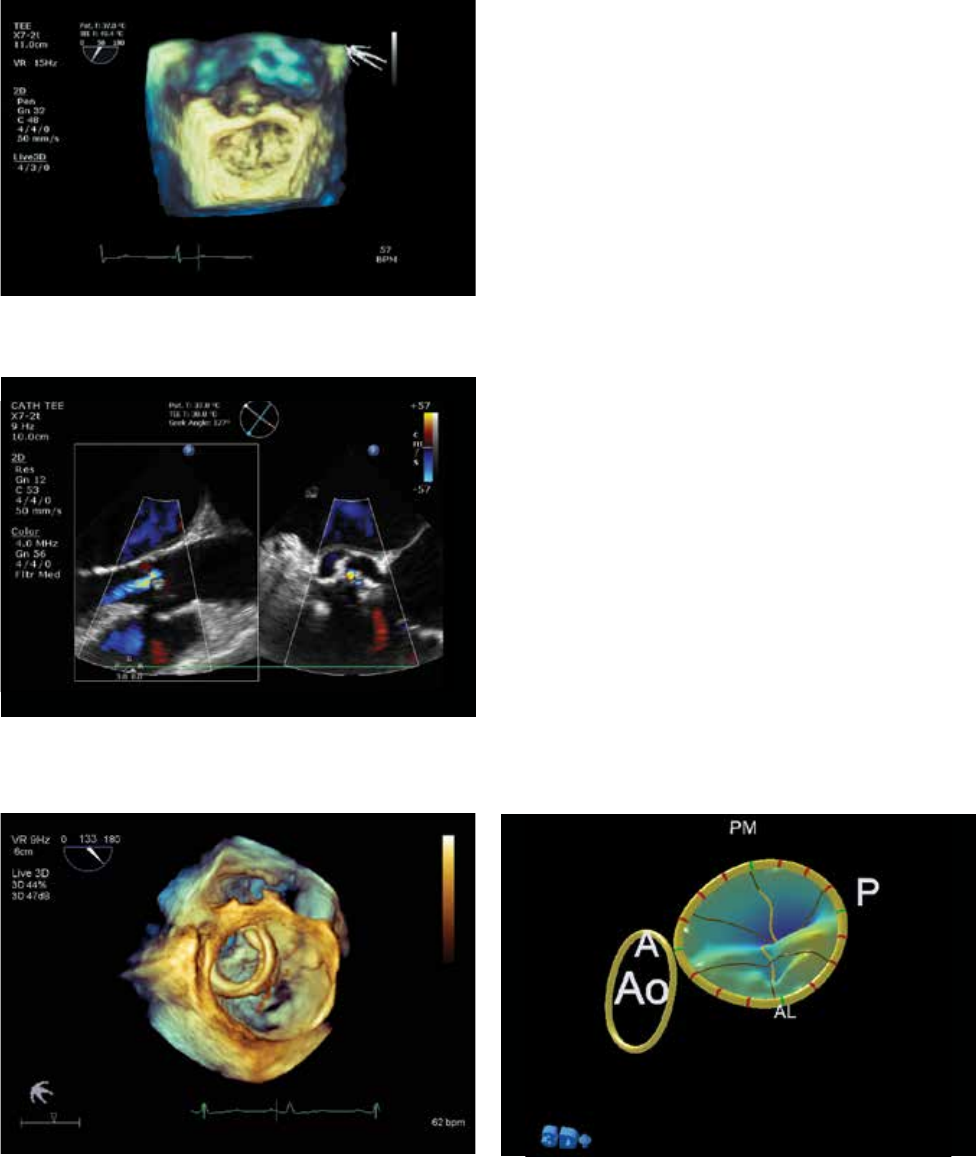

Live 3D TEE image clearly showing deployment

of ASD occluder device.

Live 3D TEE on CX50 xMATRIX supports complex

structural heart disease interventions.

Live 3D TEE goes portable

Live 3D TEE is supported on the CX50 X7-2t TEE transducer,

combining the 3D power of xMATRIX and the exceptional

image quality of PureWave crystals to capture and display

stunning views of the heart that are not available with 2D

echo. Intuitive manipulation tools allow you to measure,

rotate, crop and slice data to derive the views most

appropriate for your diagnoses, planning, and follow-up.

Live 3D TEE image of the mitral valve.

Live xPlane imaging provides real-time simultaneous

longitudinal and short-axis views of this aortic insufficiency.

Live 3D TEE supports a clear appreciation of catheter

positioning in this hybrid OR procedure.

MVN model derived from Live 3D TEE of the mitral valve.